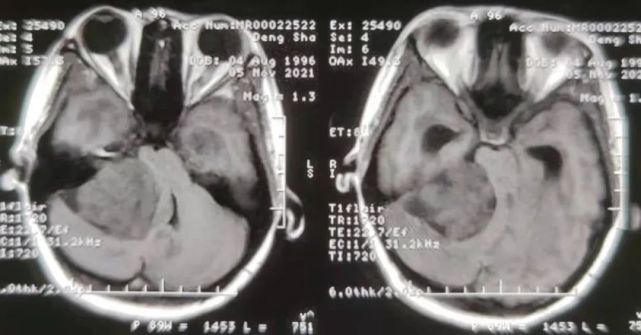

经神经外科医生诊断,患者为巨大颅内听神经瘤、脑积水合并晚期妊娠,同时还有10余年的乙肝病史……

11月6日,省医院神经外科门诊来了一位年轻的孕妈妈。她视物模糊、右下肢无力、无法独自行走。“刚开始是头昏头痛呕吐,右腿无力。那时候我怀孕5个多月了,我还以为是妊娠反应呢。”患者苗苗(化名)告诉医生,这种状况已经持续两个多月了。后经当地医院检查,发现小脑角区巨大占位,怀疑为听神经瘤,遂来省医院就诊。

经神经外科医生诊断,患者为巨大颅内听神经瘤、脑积水合并晚期妊娠,同时还有10余年的乙肝病史,因为没有积极治疗,肝功能欠佳。